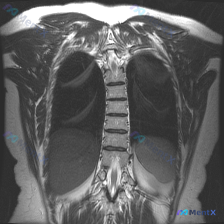

整理到一个很有意思的影像读片材料: 一张胸部MRI-T2序列冠状位影像,原始的影像学分析写的是“胸廓、脊柱、纵隔及肺野解剖结构基本正常,未见明显的病理性高信号改变”,甚至明确提了“椎体信号均匀,骨皮质轮廓清晰,未见明显骨质破坏”。 但拿到这份材料的人,第一眼观察到的线索是——脊柱侧弯(Scolios...